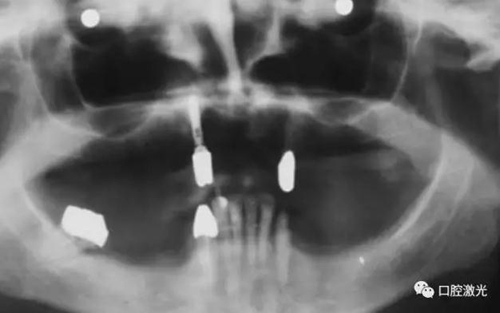

患者女性,43歲。在18年前在13位置上安裝種植體。整個(gè)上顎除23外,牙盡缺失。安裝種植體后,在種植體及23上固定套筒冠義齒。3年后患者發(fā)現(xiàn)刷牙時(shí),臨近13有大量出血現(xiàn)象。通過探針檢查發(fā)現(xiàn)深度達(dá)6mm。

對(duì)患者實(shí)施局部麻醉,隨后在種植體位置進(jìn)行翻瓣。利用塑料刮治器將肉芽組織清除干凈,并將翻瓣邊緣削薄。此時(shí)在種植體周圍可見明顯骨缺失。

治療6個(gè)月后恢復(fù)情況

治療十年以上恢復(fù)情況